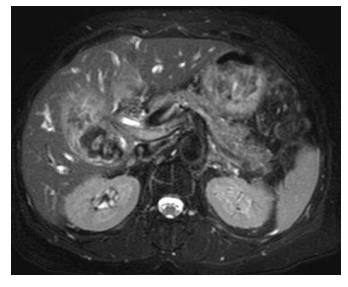

Uma paciente de 69 anos de idade, portadora de diabetes tipo 2, hipertensão arterial e hipotireoidismo, com história de IAM em 2017, apresenta quadro de icterícia progressiva, colúria, acolia, dor abdominal em hipocôndrio direito e perda ponderal de 5 kg no último mês, com inapetência e queda do estado geral. Aos exames, Hb 9 g/dL, leucócitos 12.000/mm3 , amilase 80 U/L, TGO 250, TGP 190, bilirrubina total 11 mg/dL, bilirrubina direta 9,5 mg/dL, fosfatase alcalina 320 mg/dL, gama GT 400 mg/dL e PCR 2,5 mg/dL. Ao exame físico, dor à palpação de epigástrio e hipocôndrio direito, sem DB. Realizou uma ultrassonografia de abdome, que mostrava dilação de vias intra e extra-hepáticas, com espessamento de vesícula biliar. Complementou a investigação com ressonância magnética. Mostrou a imagem a seguir.

Com base nessa situação hipotética, é correto afirmar que a